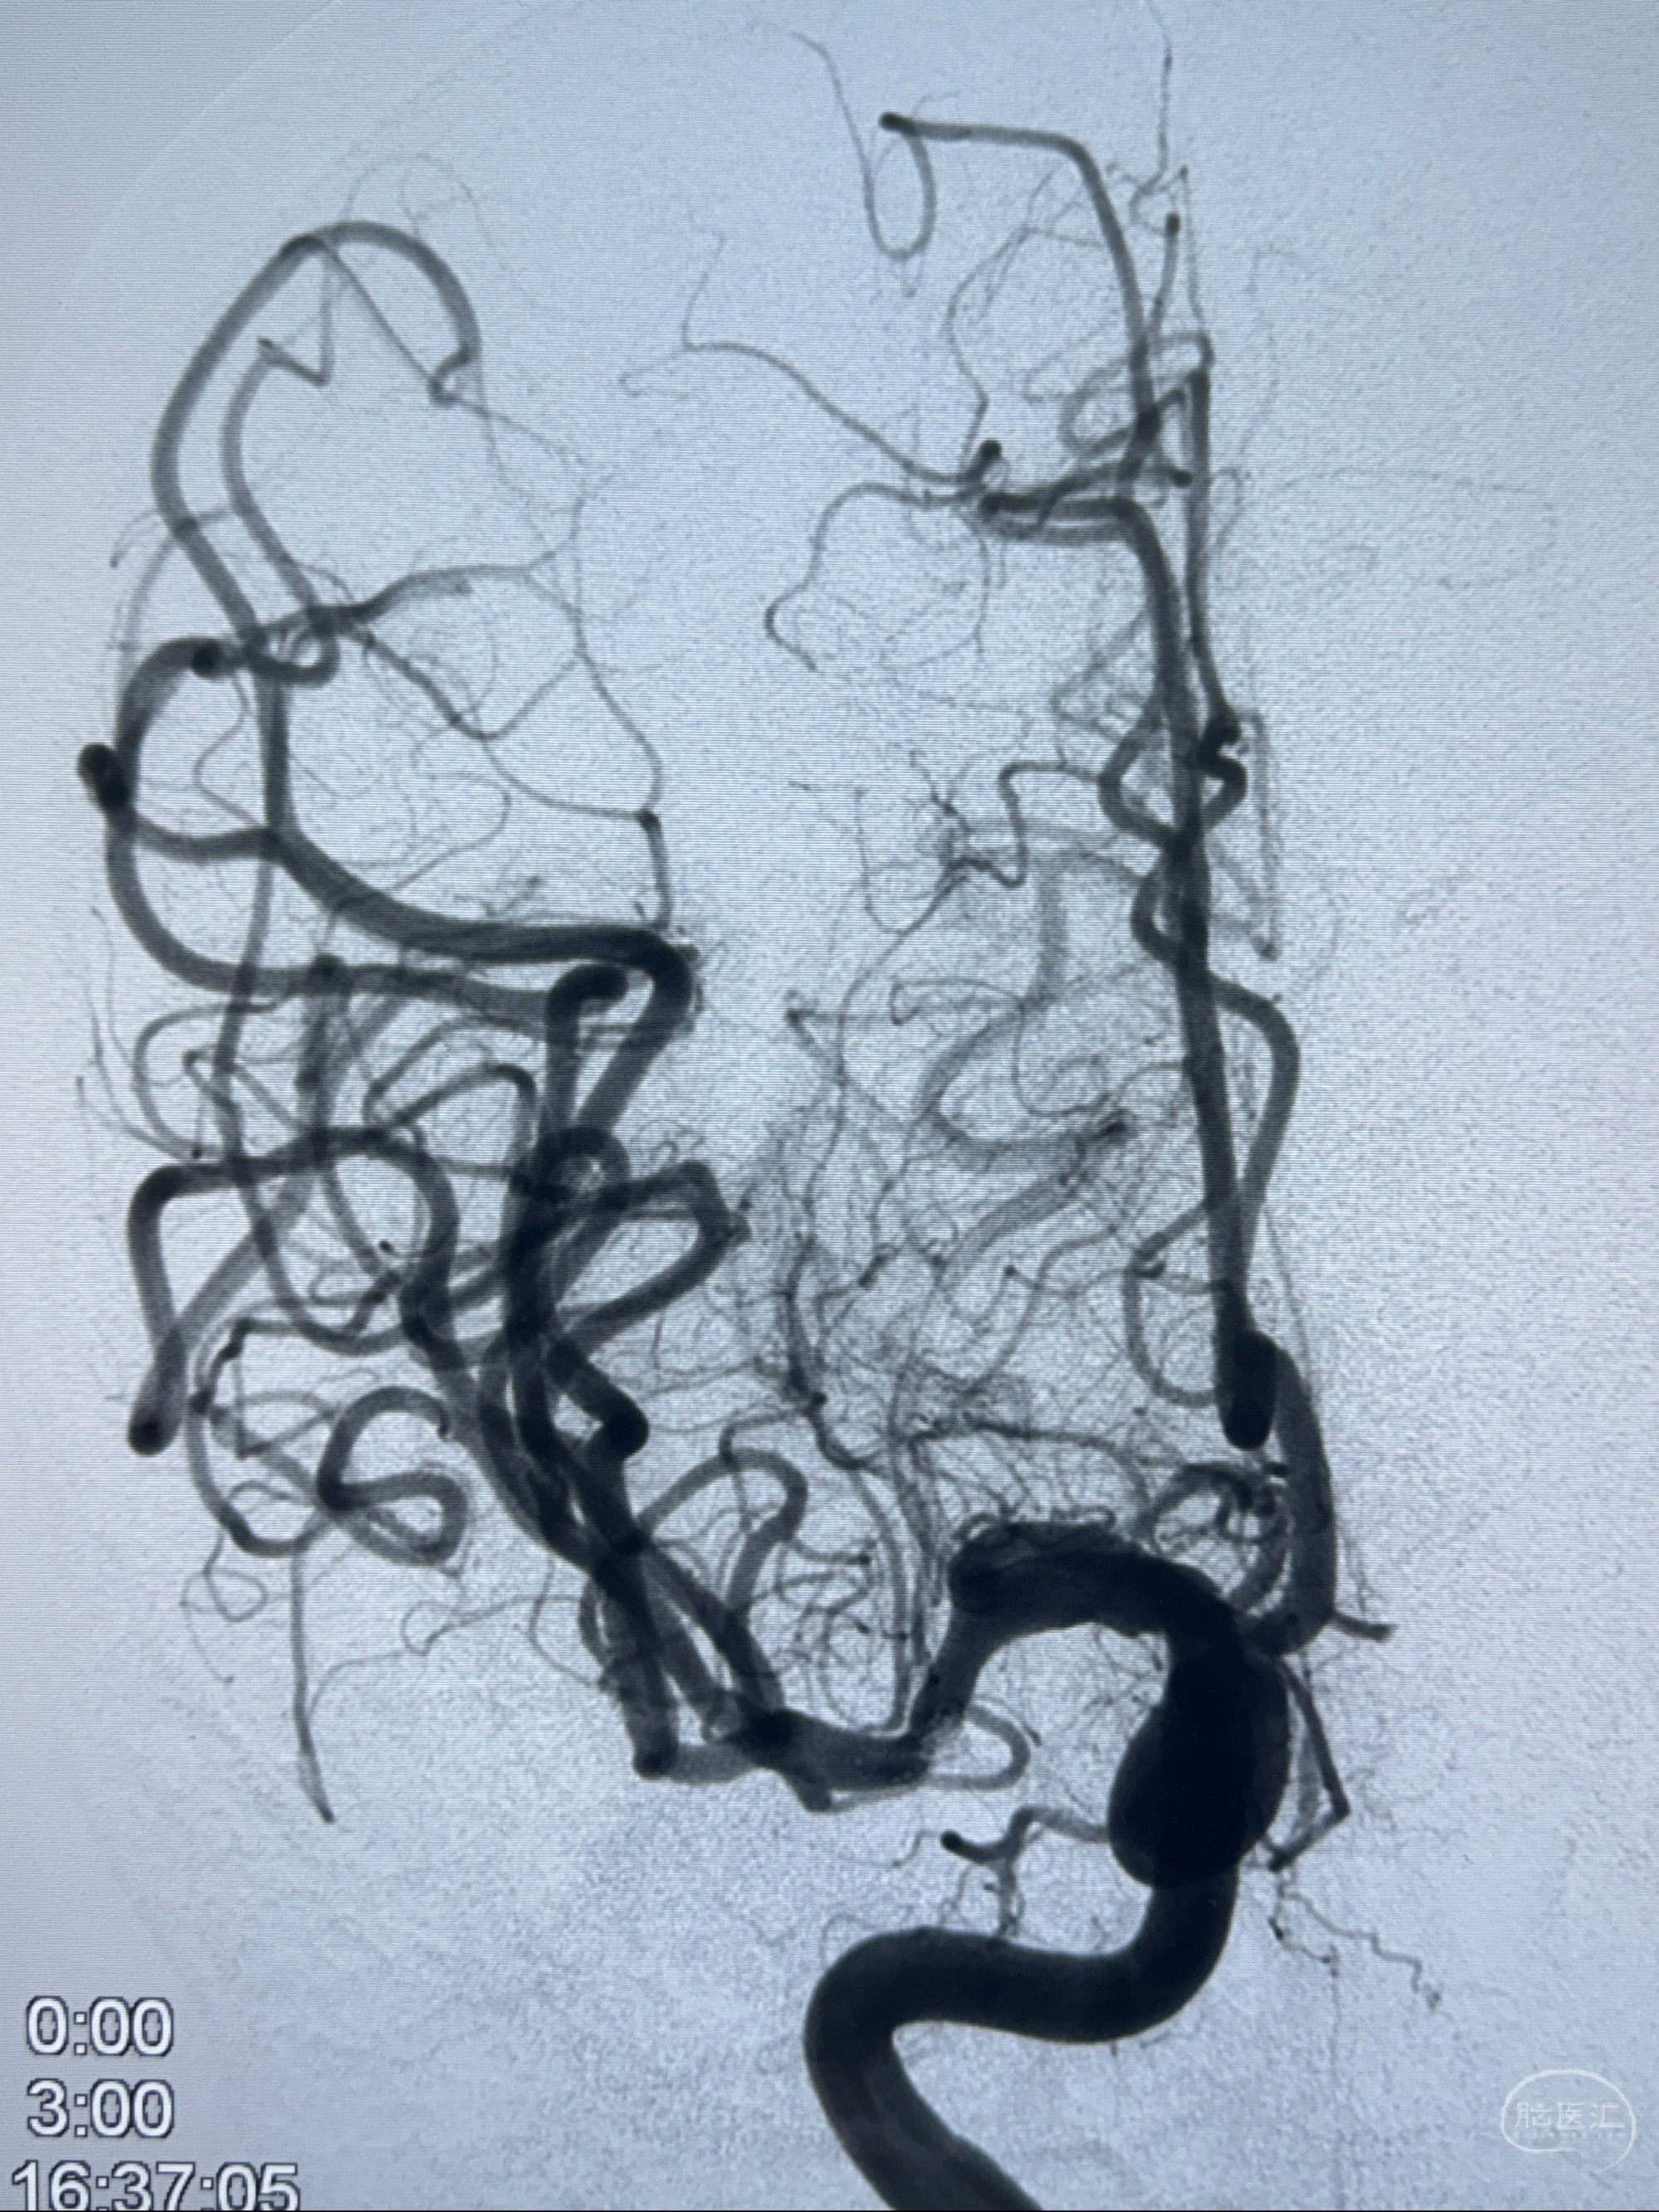

2023-11-24DSA:右侧大脑中动脉下干起始部动脉瘤,约2.3*2.5mm,形态规则

2023-12-04全麻下行支架辅助治疗

S-AB4-20mm

麻醉苏醒佳,遵嘱动作

术后即刻CT